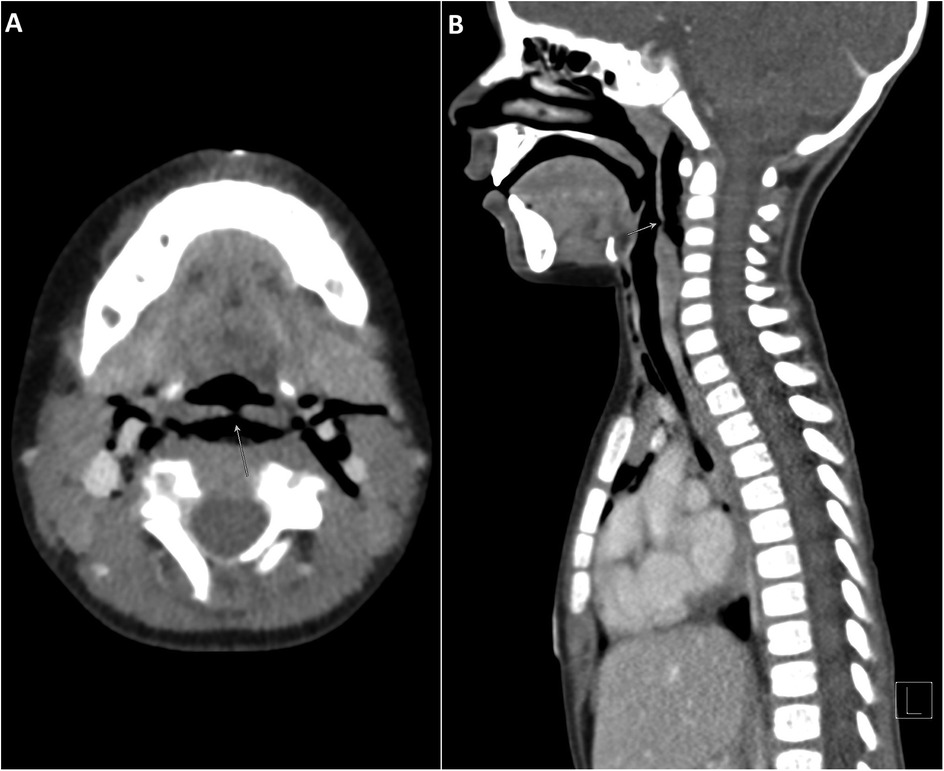

Oropharyngeal injuries in young children, though common, carry the potential risk of serious complications. Here, we describe a rare case of a toddler with a minor penetrating injury in the hypopharynx leading to perforation, surgical emphysema and pneumomediastinum. A 2-year-old boy was brought to the emergency department with noisy breathing and shortness of breath started after a traumatic injury with a pencil in the mouth. He was found to have tachycardia, tachypnea, grunting but no stridor or retractions. A brief oral exam showed a blackish discoloration in the posterior pharyngeal wall, and crepitations were palpated on the neck. Imaging revealed extensive subcutaneous emphysema and a defect in the posterior oropharyngeal wall. He underwent surgical repair of the pharyngeal defect and was later discharged in stable condition. This case highlights the need for vigilance in assessing oral impalement injuries in children, as such injuries can lead to significant complications. Early detection and management is crucial to prevent severe outcomes. The case underscores the importance of careful clinical and radiological evaluation in managing pediatric oral impalement injuries.